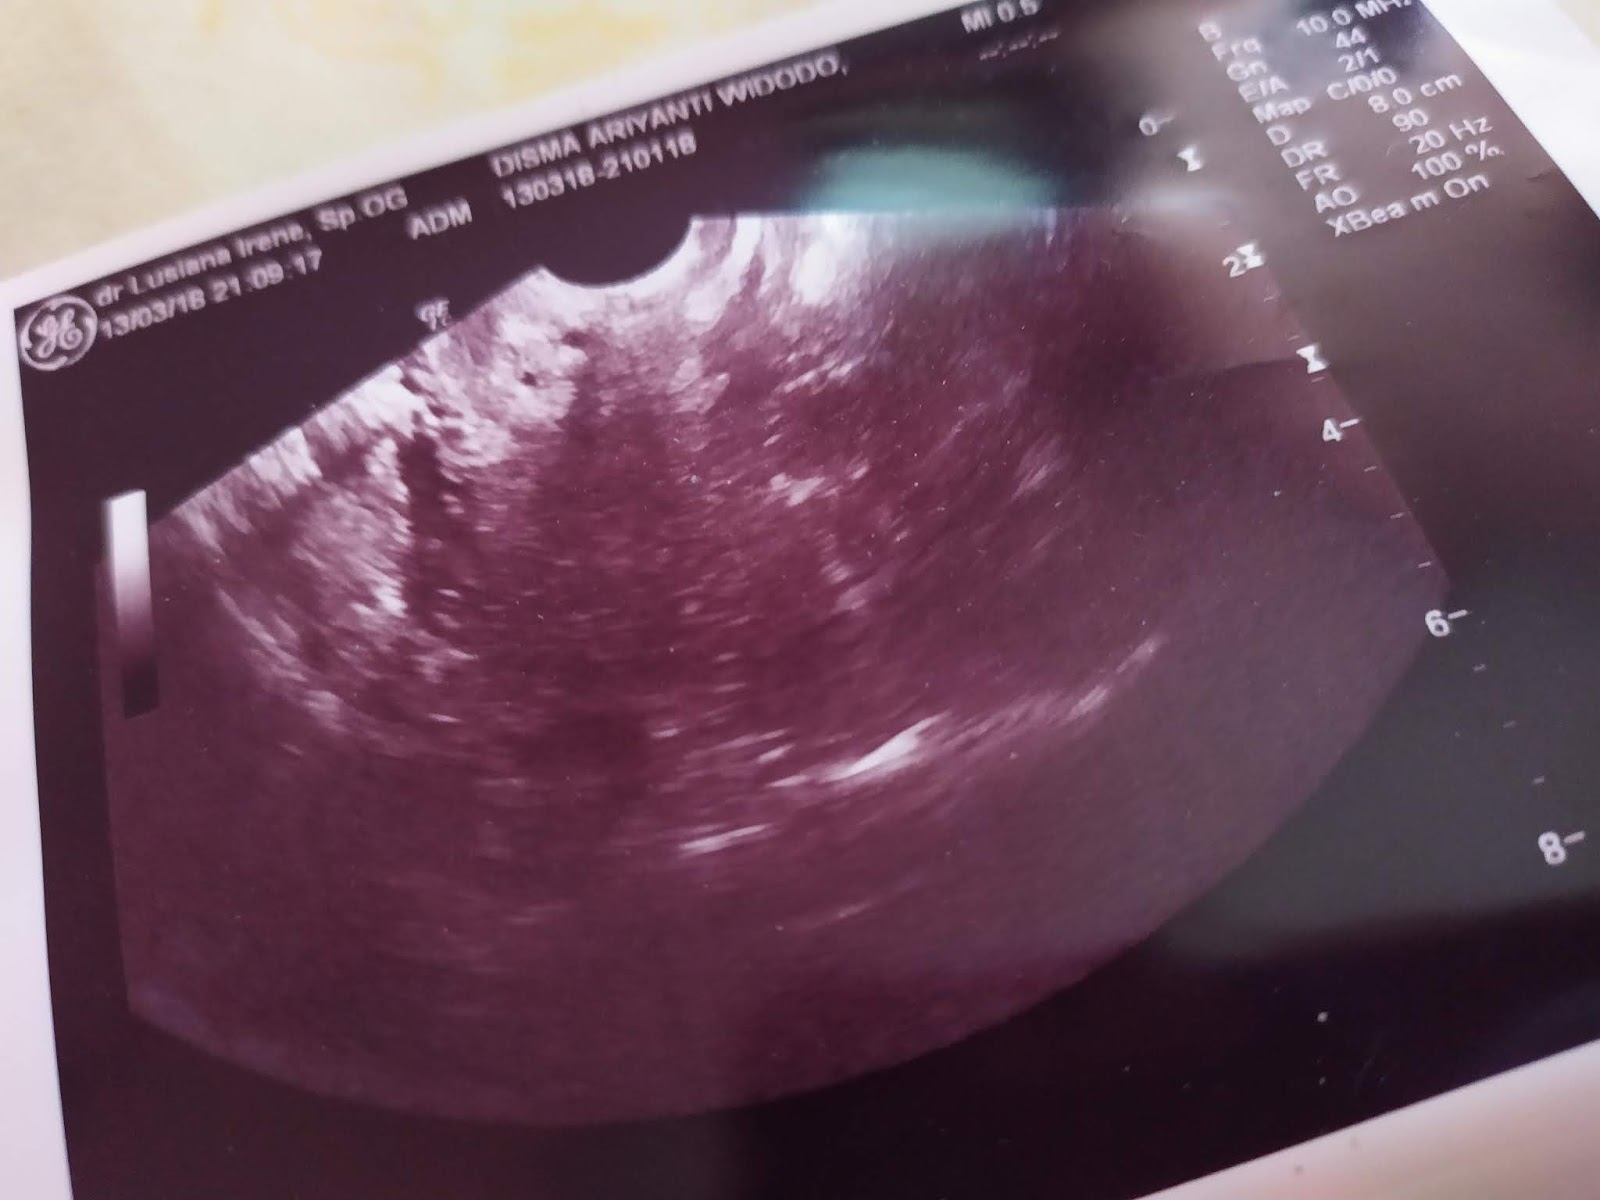

Gambar Usg Sel Telur Matang

BEGINI GAMBAR SEL TELUR YANG SUBUR… - dr Yudhistya SpOG | Facebook Story of My Journey: TTC Journey #2 USG Folikel dan Hasil Analisa Sperma Aku dan PCOS (Hasil USG Trans Vaginal) - JalanSenja.com Cerita Promil 4 - Polycystic ovary (PCO) - Fika Putri Cerita Promil 2 - USG Transvaginal dan Tes Sperma - Fika Putri Semua Akan Terjawab di Waktu yang Tepat - kumparan.com Promil Story : MIMPI BURUK ITU BERNAMA PCOs - The Arsalan Family Journal Penting Dilakukan Wanita, Ketahui Sel Telur Dalam Tubuhmu Jangan Sampai “Mandul” Karena Kehabisan Program Hamil di Dokter Lusiana Irene, SpOG Jogja Manusia sedikit tahu..sel telur kecil tidak mungkin hamil | Dr Suryo, SpOG - Kesehatan Reproduksi C e r i t a C i k i: Sel Telur Kecil-Kecil EFEK PENYUBUR Pada wanita normalnya sel… - dr Yudhistya SpOG | Facebook Ikhtiar yang ke dua – Part 2 (H6-H11) – Bread and Butter Letter Promil Step 4 – Baby Journey PCOS adalah… | Kisah Ibuknda (pakai ‘k’) :D Room | ‘Aisyah Tsurayya Inart’s Story - Yah, Saya Akhirnya Hamil - I’m 1 In 10: My PCOS Story Kisah Perjuangan Terbaru Tya Ariestya Saat Jalani Program IVF | Popmama.com story of my lyfe: pejuang keturunan Nikita Mirzani Bagikan Hasil USG Bayi Kembar, Dapatkah Gen Kembar Diturunkan? - Semua Halaman - Intisari lihat hasil USG tranvaginalku wktu bulan Januari 2013 apa itu PCO? - IbuHamil.com Cerita Promil 4 - Polycystic ovary (PCO) - Fika Putri aq PCO bund, ada yg bisa bantu baca hasil USG intravagina q??? - IbuHamil.com Hasil USG Sel Telur Yang Subur - YouTube Pengalaman Bayi Tabung/ IVF (Part II) Update with Pict! | honeymenulis’s Blog Inart’s Story - Yah, Saya Akhirnya Hamil - Story of My Journey: June 2017 Ingin Terhindar dari Kista? Jauhi 4 Jenis Makanan Enak Ini Sekarang! - Semua Halaman - Grid Health Program Hamil Bulan ke-1 : PCOS Survivor | Lanalouie Embrio 3 cm berapa minggu. minggu: bayi Anda sebesar tongkol jagung BEGINI GAMBAR RAHIM YANG SUBUR… - dr Yudhistya SpOG | Facebook PCOS | medicalstudentnotes USG Transvaginal: Penjelasan, Prosedur & Manfaat (Lengkap) | Friso BILIK SONOGRAFER : Kista Ovarium Kontrol H+10 (Cek Perkembangan Sel Telur) Istilah kehamilan dipertimbangkan dengan USG. Kehamilan kebidanan dan embrio Selamat Pagi Senin Ayah Bunda. Semoga… - Dokterkandungan. id | Facebook My First USG | Story of Us Menuju Hamil – Part 2 of 3 – Edward Suhadi Apa itu PCOS? Kenapa Sulit Hamil? | Sunshine of My Life Setiap Ibu Hamil Harus Tahu, Kapan Harus Melakukan USG lewat Vagina? - Semua Halaman - Nakita Program Hamil di Dokter Lusiana Irene, SpOG Jogja Saat Sel Telur Berukuran Kecil dan Sulit Dibuahi - Health Liputan6.com Kabar Gembira, Ini Tanda Awal Sel Telur Berhasil Dibuahi oleh Sperma | Popmama.com 101+ Gambar Cek Sel Telur Paling Hist - Gambar Pixabay Kontrol H+12 (Mendebarkan, apakah sel telurnya tetap berkembang?) Program Kehamilan Balasan dari Saya Penderita PCOS, Saya Berhasil Hamil | KASKUS Pembekuan Sel Telur: Fungsi, Prosedur, dan Komplikasi INGIN HAMIL – Siklus Ovarium dan Tanda-Gejala Wanita Subur | JuliantoWitjaksono.com 6 Fakta Mengejutkan Tentang Sel Telur Wanita - YouTube Pengalaman Hamil Kembar - The Urban Mama Maimuns — PCOS? Deal with it! Berapa Sisa Sel Telur di Tubuh? Bisa Dicari Tahu | Parenting.Dream.co.id PCOS Polycystic Ovary Syndrom Apakah… - Komunitas Impian Bunda | Facebook Persiapan Hamil (4) – jurnal Ammi Wanita Hasilkan 2 Sel Telur dalam Masa Ovulasi, Bisakah Terjadi? Promil Story : MIMPI BURUK ITU BERNAMA PCOs - The Arsalan Family Journal My journey to motherhood: HSG, Tes Sperma, hingga PCO Polikistik Ovarium (PCOS): Haid sering tidak datang, Berkumis, Berjerawat, Ingin hamil sulit | Dr Suryo, SpOG - Kesehatan Reproduksi PCOS dan Metformin. Sohib karib! – Cerita Bumi Blighted Ovum | ~cahaya kebaikan~ Cerita Pengalaman Kehamilan Pertama dan Persiapan Melahirkan Anak Pertama - For The Love of Foods and Beauty Masih banyak yg belum tau.. INSEMINASI… - Bayi Tabung PMC Pekanbaru Cerita Program Hamil dengan Dokter Enny Sp.OG di Yogyakarta ~ Land of Jenganten Semua Akan Terjawab di Waktu yang Tepat - kumparan.com Fika Putri Berbagi Tips: Cara Mengetahui Masa Subur Wanita Berdasar Penghitungan serta Ciri-Cirinya - Garda Remaja GAGAL OVULASI?? SERING TERJADI PADA… - Konsultasi Promil Cepat Hamil dan Alami | Facebook Yosevina Issabela prosespersalinan Instagram posts (photos and videos) - Picuki.com Apa sebetulnya bayi tabung dan bagaimana proses menjalaninya? – Bayi Tabung Penang Di minggu kebidanan mana embrio terlihat. Minggu berapa embrio terlihat pada USG? Apakah prosedurnya aman pada tahap pembentukan anak PCOS itu Variable dan Sangat Rumit Prosedur Bayi Tabung: Sebelum dan Sesudah Mengikutinya - Smarter Health Mengenal Kehamilan Kosong atau Blighted Ovum (BO) - Kompasiana.com Cerita Promil, Perjalanan menuju kehamilan (long story short, I finally got pregnant) - Nyonyah Intan Sindrom Ovarium Polikistik (PCOS) 4D Gallery | Dr Suryo, SpOG - Kesehatan Reproduksi Kapan USG direncanakan selama kehamilan. Apakah saya perlu mempersiapkan prosedur? Keadaan organ reproduksi wanita Irish Bella Hamil Anak Kembar, Sang Ibunda Tak Sangka Bakal Punya 2 Cucu - Halaman all - Tribun Batam Lapsus Kista Ovarii - Apriamalia - [PDF Document] Success story – GLADIOOL IVF RS Indosehat Solo, Jl Solo Sragen Km 11, Kebakramat, Karangdawa (2020) Saya Penderita PCOS, Saya Berhasil Hamil | KASKUS September 2014 - Pipit Widya Aku dan PCOS (Hasil USG Trans Vaginal) - JalanSenja.com Pengalaman PCOS-ku yang Berhasil Hamil Alami - kumparan.com Apakah USG mempengaruhi kehamilan. Bagaimana ultrasound mempengaruhi embrio? Ultrasonografi dilakukan hanya atas kesaksian dokter atau mungkin atas permintaan ibu BAB III - [DOCX Document] Kista Ovarium. - ppt download Biaya USG 3 & 4 Dimensi di Karawang - Perawatan Kesehatan Cerita Pengalaman Kehamilan Pertama dan Persiapan Melahirkan Anak Pertama - For The Love of Foods and Beauty Wanita Punya 400 Sel Telur Setiap Menstruasi, Kenapa Susah Hamil? - Semua Halaman - Nakita Tragis Si Ibu Hamil Dibunuh, Bayi di Dalam Kandungan Dicuri - Halaman all - Warta Kota Perlukah USG Transvaginal saat Program Hamil? | Popmama.com 13 Tanda - tanda Kehamilan Awal yang Bisa Dipercayai - Mamapapa.id Melahirkan bayi kembar pada minggu-minggu kehamilan. Dapatkah dokter tidak melihat bayi kembar dengan USG: diagnosis dini kehamilan ganda PROSES DAN BIAYA INSEMINASI 1. USG USG… - dr Yudhistya SpOG | Facebook